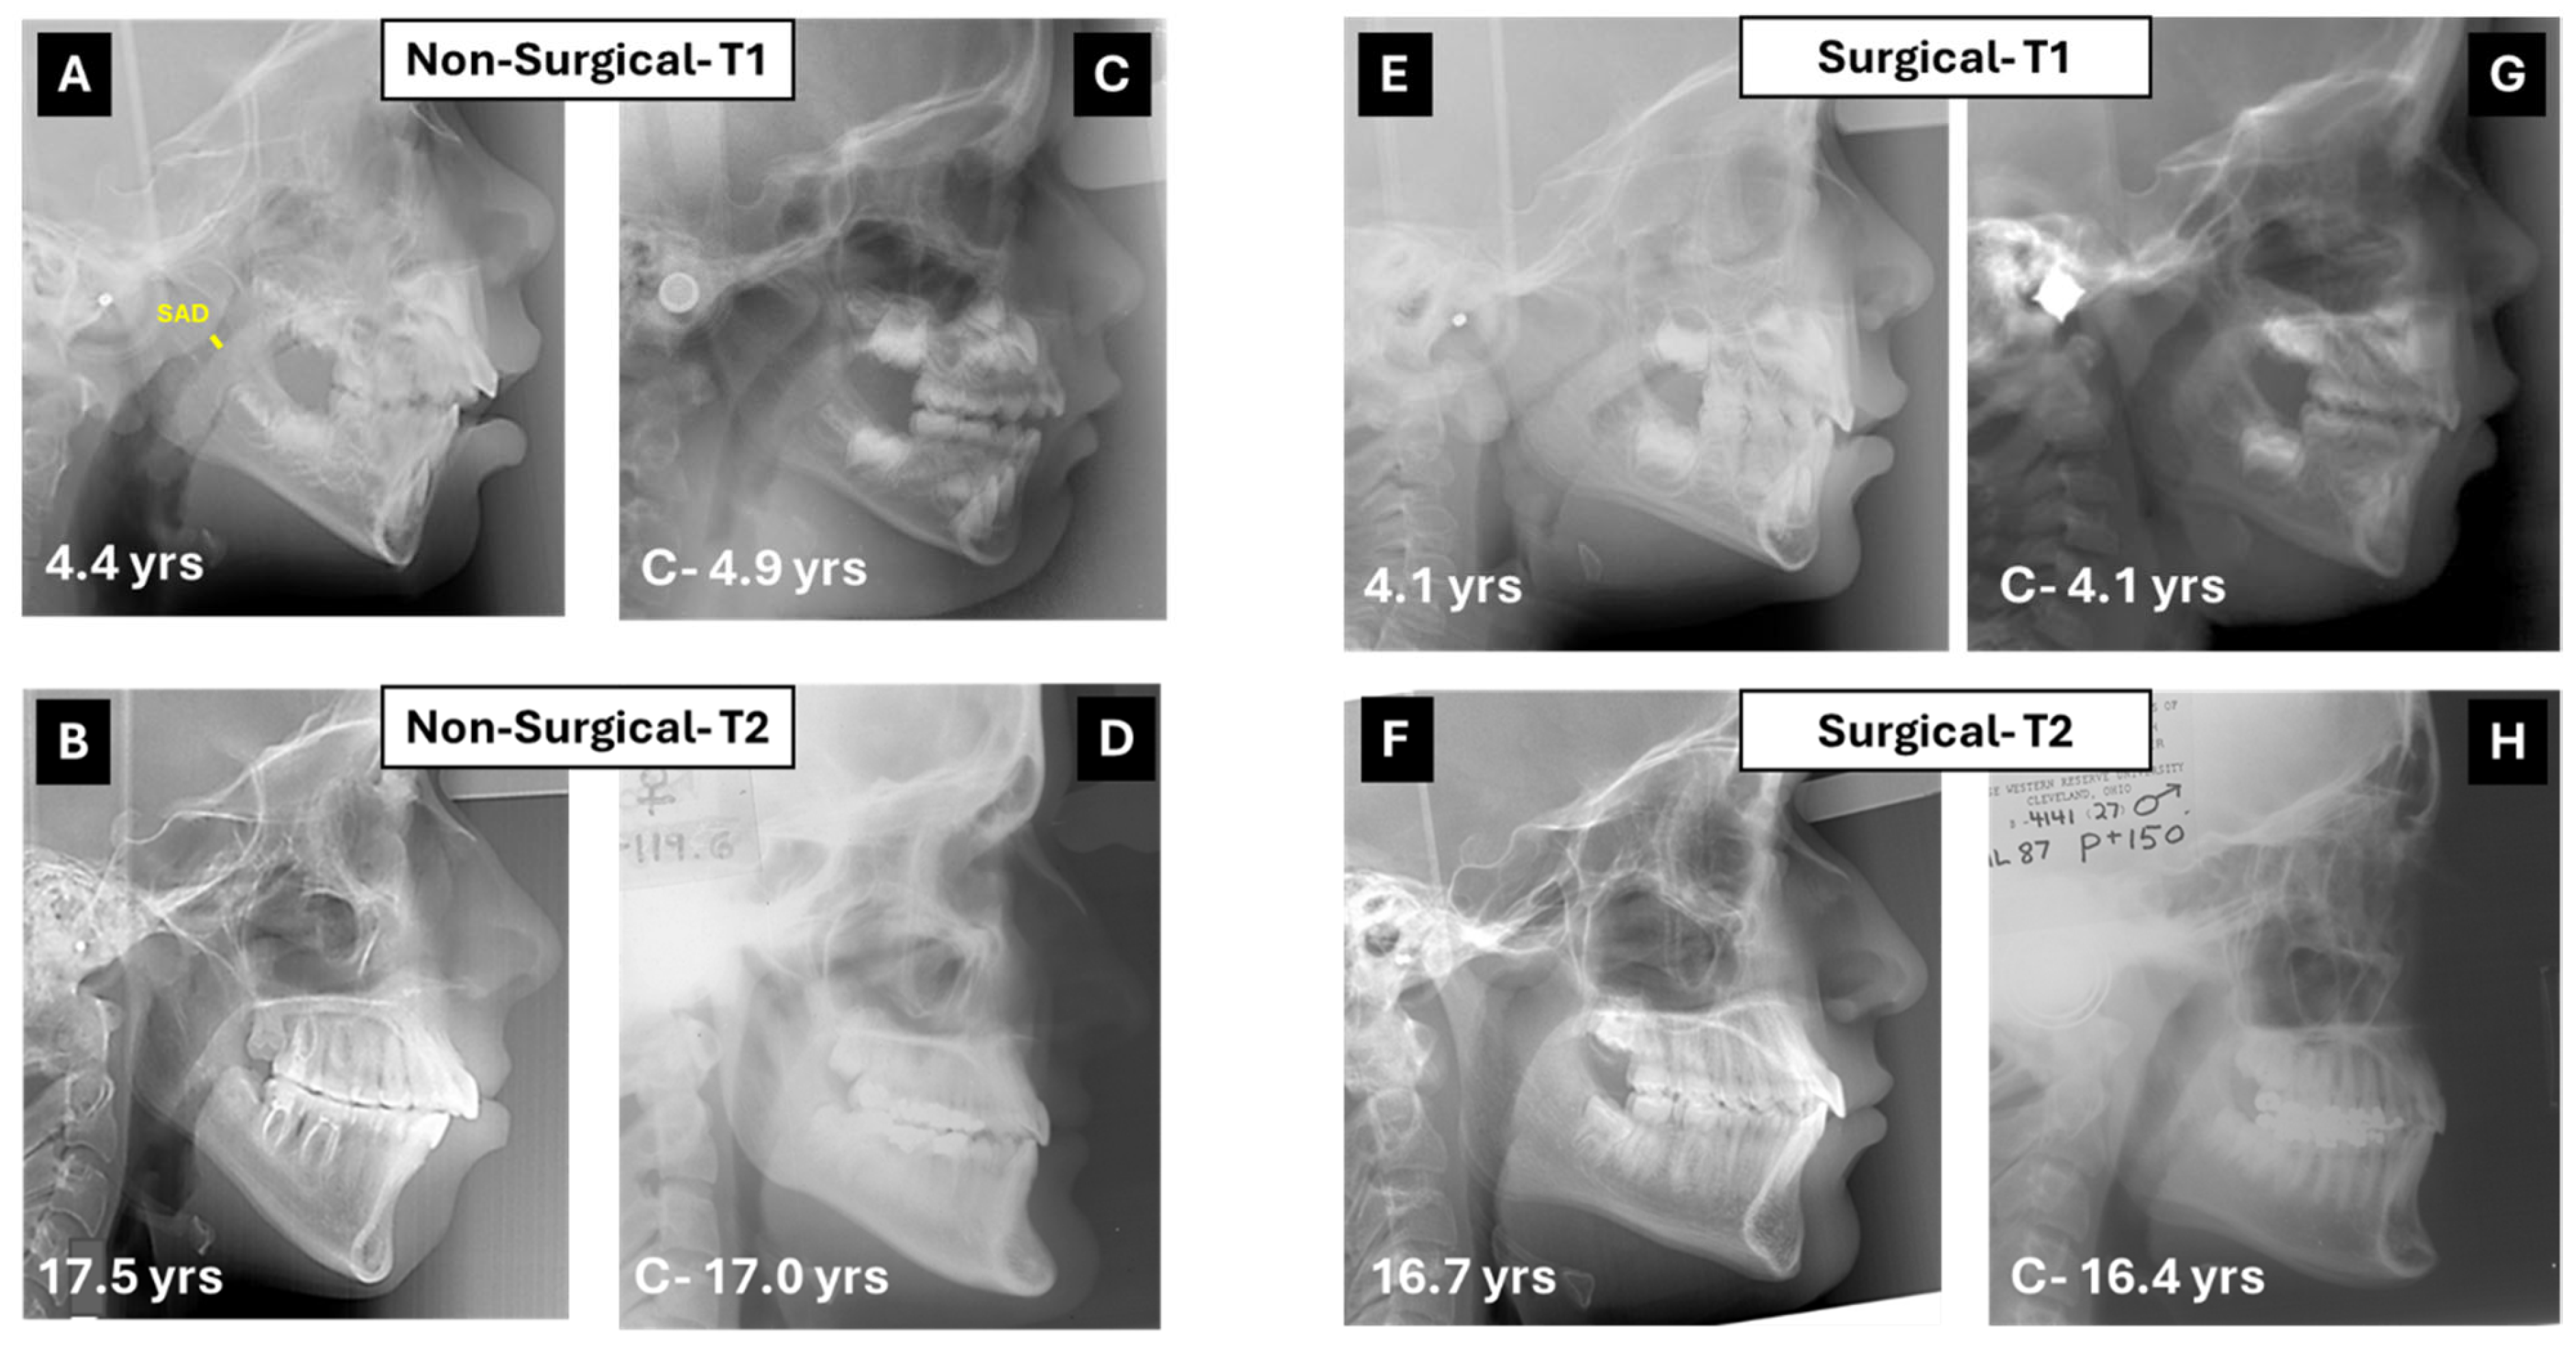

- Medical and surgical treatment can be beneficial, as both showed improvement in facial cephalometric features; however, surgery resulted in more improvement in mandibular shape and position. While the mandibular angle (Ar-Go-Me) closed in both treatment groups, the T2-T1 difference was statistically significantly greater in the surgical group (nearly 5°, Table 1). The closure indicates anterior rotation of the mandible and decrease in mandibular plane divergence. The consequent flattening of facial convexity (S-N-Me) was significantly greater in the surgical than the non-surgical group (T2-T1 difference = 4.4°, Table 1), further accentuating the efficacy of surgery (Figure 3).

- The patients who underwent surgery had more severe facial characteristics and were younger at pre-treatment (5.31 ± 1.99 years vs. 6.77 ± 2.84 years in surgical and non-surgical groups, Table 1). This initial condition may have been the reason for the otolaryngologist to perform and the parents to accept surgery. Treatment selection reflects the protocol followed by the treating otolaryngologist, technically indicating a selection bias, even if unavoidable in reference to the pertinent protocol. Consequently, the differences observed between groups may be attributed not only to the treatment modality but also to the initial severity of the condition, suggesting that severe obstructions are diagnosed early and are eligible for surgical treatment to reach the improvements observed in this study.

| SAD mm | 4.39 | 2.95 | 11.84 | 2.81 | 0.00 | 2.96 | 2.49 | 16.25 | 2.94 | 0.00 | 7.45 | 3.31 | 13.29 | 3.22 | 0.00 |